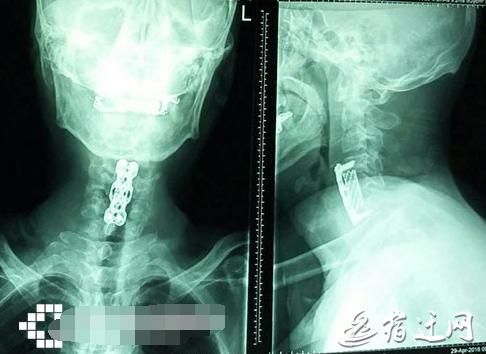

53岁大伯仰头喝可乐突然四肢瘫痪

“颈椎病是一个由量变到质变的过程。事后我们询问,他说自己早前就有脚麻、走路时脚踩棉花的感觉,这是脊髓型颈椎病的典型症状,但他一直没重视?!宾囊缴?。

经过治疗,王大伯的腿可以微微抬一抬了,但想要下地扶拐走路,还要等上半年。躺在病床上的王大伯感慨,“我再也不想喝可乐了。”

颈椎不适持续72小时应就医“王大伯的遭遇也提醒大家,平时要保护颈椎,要少喝碳酸饮料。”瞿医生说,尤其是躺在床上、坐公交车、吃饭前都喜欢掏出手机刷朋友圈的低头族,颈部肌肉力量长时间不平衡,会造成颈椎生物力学的改变。